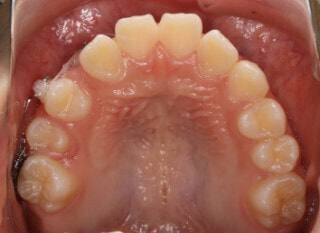

小児期第二段階

開始時

小児期の第二段階